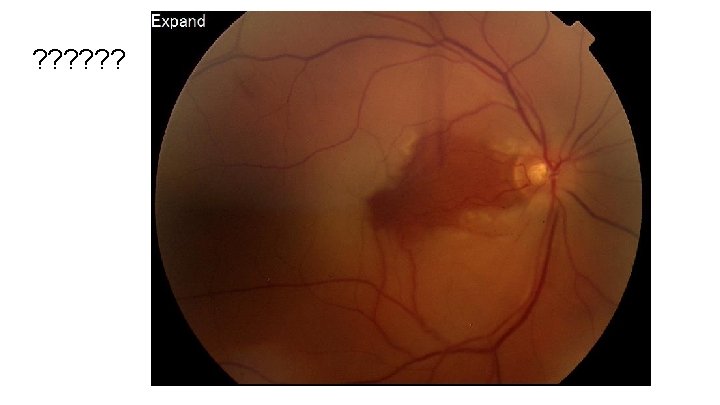

Kissing choroidals (Choroidal hemorrhage)

Kissing Choroidals